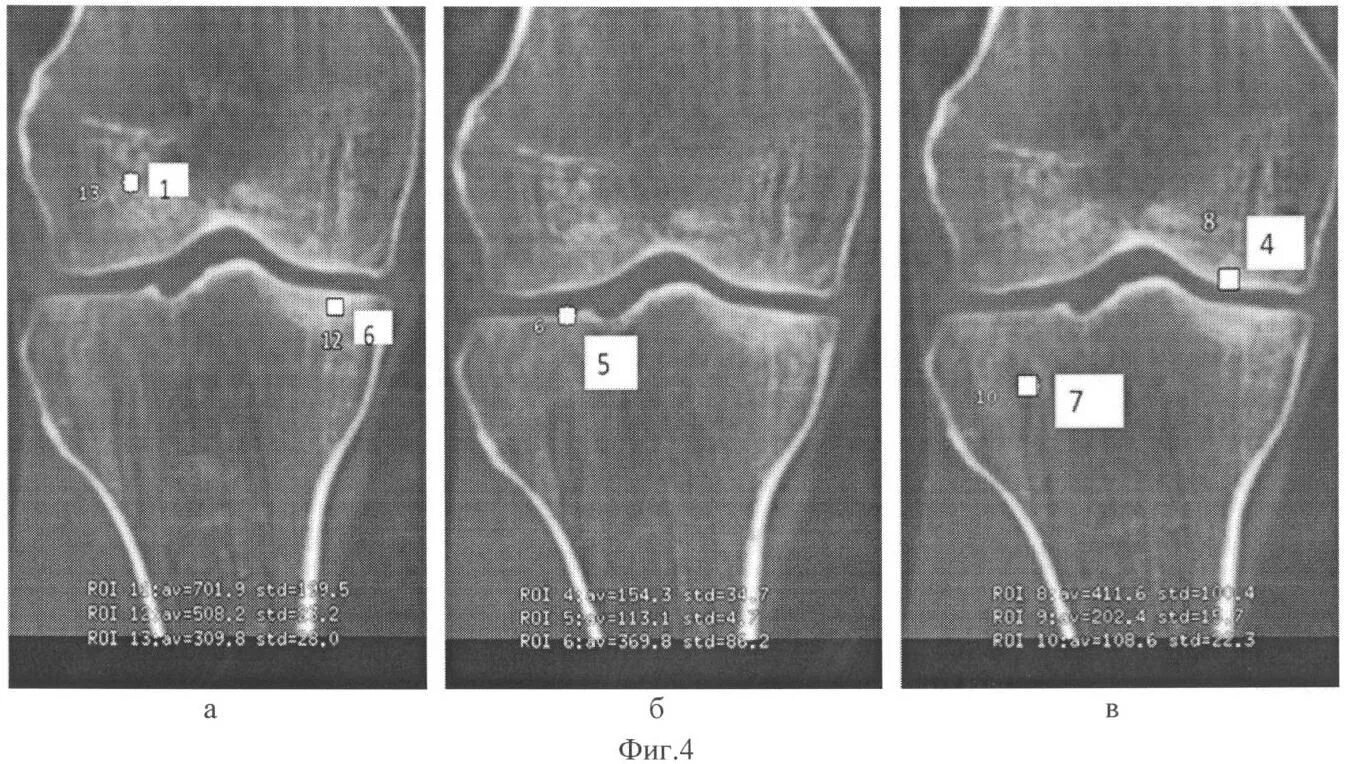

Гонартроз мрт